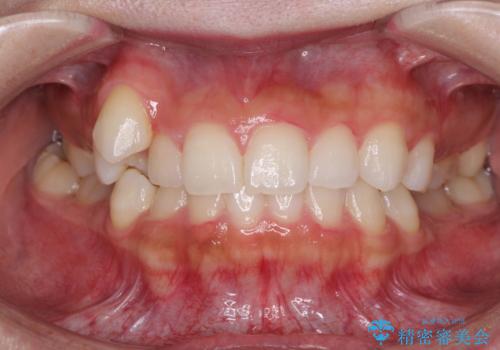

八重歯を改善 目立たないワイヤー装置での矯正治療

- 八重歯を気にして来院された患者様です。

本来であれば八重歯の隣後方の歯を抜歯するのですが、その後ろの歯が乳歯であり後続永久歯もなかったため、乳歯を抜去することとしました。